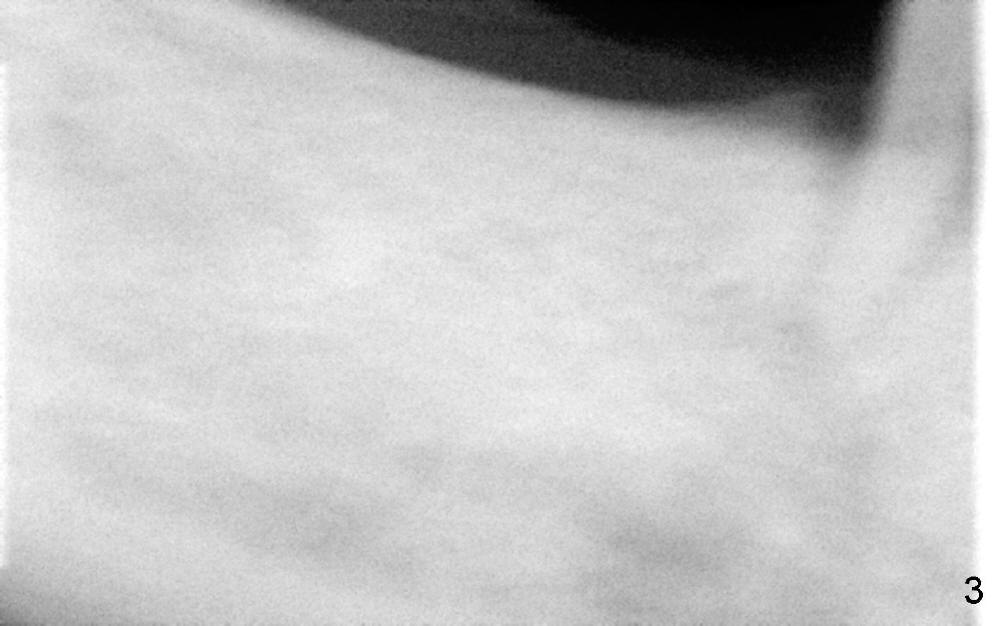

To avoid paresthesia on the right side, several preop PAs are taken (Fig.1-4) so that we know how to take good X-ray for this gagging patient.  At first, #2 Sensor is used to take the first PA (Fig.1).  It does not show the apex of the tooth #29.  The second PA is a little better (Fig.2), but the mental nerve is out of view.  Then #1 sensor is used.  It allows us to position the sensor lower (Fig.3), but the image is blurred.  When it is retaken, the image is clear (Fig.4), showing the proximity of the mental nerve loop (Fig.4': red dashed line) to the root tip of the tooth #29 (R).